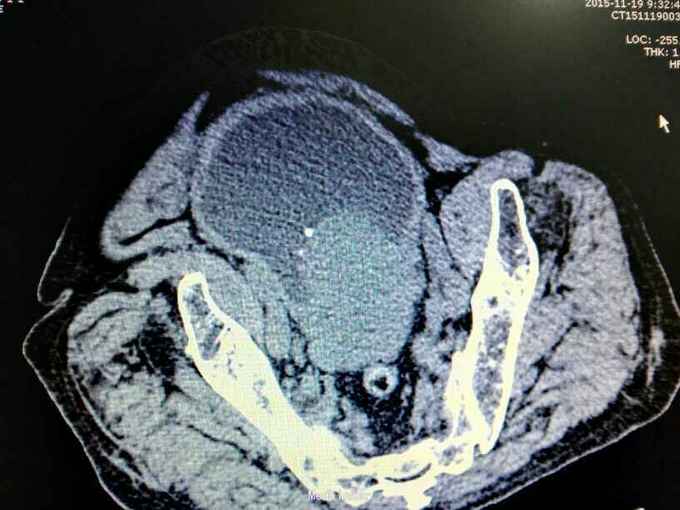

男性,87岁,进行性排尿困难10年,小便不能自解2天入院。无血尿,无发热、腰痛。一直口服藏药治疗前列腺增生症。既往无高血压、糖尿病。

腹部明显膨隆。耻骨上膀胱区扣浊。肾区无扣痛。尿常规少许白细胞。肌酐506,电解质正常。Hb116。

前列腺增生症 尿潴留 双肾积水 肾功能不全,膀胱结石,尿路感染,双肾多发囊肿。给予留置导尿,间断分次放尿后,出现肉眼血尿,持续膀胱冲洗,颜色较红,伴血凝块间断堵管。